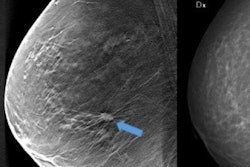

The findings suggest that CAD is a useful tool when utilized with DBT, which can increase reading time due to the fact that it produces a 3D image, wrote a team led by Dr. Eun Young Chae of the University of Ulsan College of Medicine in Seoul, South Korea.

"Interpretation of DBT studies may be challenging for radiologists partially because it involves the analysis of a series of thin slices through the breast, which requires longer reading time than that associated with FFDM [full-field digital mammography]," the authors wrote. "To address the challenges of reviewing DBT studies, computer-aided detection software may help radiologists detect cancers and improve efficiency in the DBT interpretation workflow."